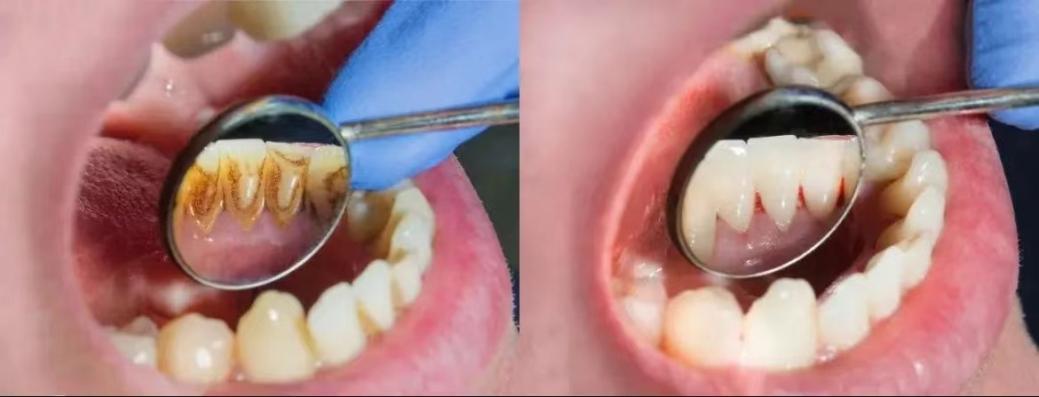

洁牙前后对比

可是许多人对洗牙有很大的误解,觉得洗牙对牙齿有损害,拒绝洁牙,害怕洁牙,今天牙医就要为洁牙摆脱冤屈,不再背锅!